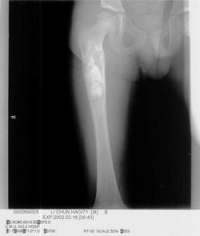

有经验的骨肿瘤医生仅凭X线平片就可以作出骨囊肿的临床诊断。病变灶为边界清晰的液性低密度灶,四壁为薄层的硬化灶壳。病变灶略向近骨骺的干骺部位扩大。病灶非偏心性,也不破坏骨外壳,更不会突破骨质形成骨膜外反应骨,除非是在病理骨折后的愈合期。有时脱落的骨皮质成份落入囊腔中,X片显示被称为“落叶征”(FallenleaforFallenfragment)。当病灶发生在骨盆,CT扫描对病灶部位及囊肿形态的判断有价值。MRI可以明确囊内富含的液性成分。骨ECT扫描表现为外周薄的浓集而中央病灶冷区。

1.好发于4-20岁,多见于5-15岁儿童,少见于成人。好发于股骨颈、股骨上端和肱骨上端。随着年龄增长,囊肿逐渐向骨干方向移动。

3.X线摄片显示长骨干腄端或骨干部位有椭圆形溶骨破坏,边界清楚,其周围可见薄层硬化带,骨皮质可有轻度膨胀变薄。

X线表现病损为界限清楚的射线透亮区,外有一薄层骨硬化边缘,由于囊肿膨胀性生长,造成骨皮质不规则变薄,X线片常呈假分叶状表现,尤多做囊肿在肱骨或股骨的干骺端向下扩展至骨干,向上扩展虽接近骨骺,但后者可被累及,病理性骨折很常见,囊肿可有骨嵴假象,病理检查见病损为单房的囊腔,其中充满清液,囊内衬以薄层纤维组织,骨折后腔内含血性液体并出现骨痂。

X线平片位于长骨干骺端,呈圆形、卵圆形或柱形,沿长骨纵轴发展,表现为轻度膨胀性生长,局部骨皮质变薄,边缘光整,无骨膜增生。合并病理骨折时,骨碎片向囊内移位,称“碎片陷落征”,有助于鉴别。

1.多发在长管骨的干骺端,病灶呈圆形或椭圆形,其长轴与长骨纵轴一致。

2.病灶于T1WI上多呈低或中等均匀信号,T2WI呈明显均匀高信号,若囊液内有出血或含胶样物质则T1WI和T2WI上均呈高信号,少数呈多房改变时T2WI上可见低信号纤维间隔。

3.病灶周边骨壳呈圆圈样低信号,一般完整,边缘清晰。局部骨皮质变薄,无骨膜反应。常伴发病理性骨折,表现为骨皮质断裂,骨片陷落而插入病灶内,称之为骨片陷落征(fallenfragmentsign),此征在T2WI上显示较清晰即在高信号的囊液中见低信号的骨片线条影。